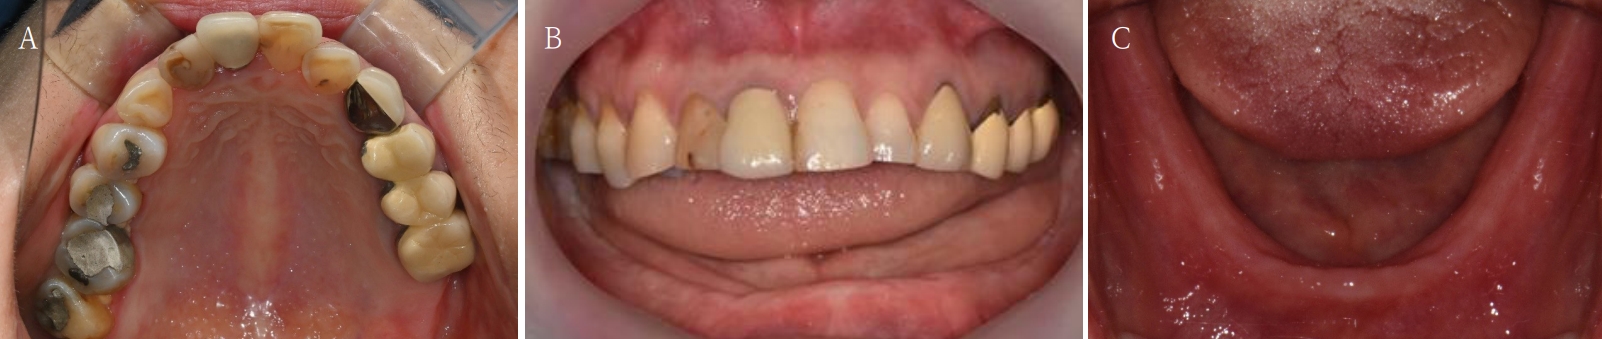

Fig. 11.

Immediate provisional restoration with 3-dimensional prinited denture is placed.

Fig. 12.

Intraoral scan with and without provisional restoration is taken. The occlusion and vertical dimension information is recorded for the final prosthesis.